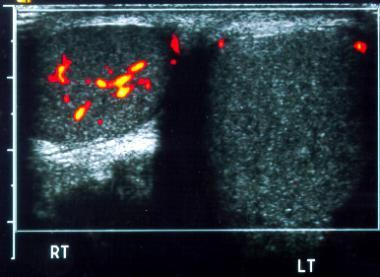

Varicocele

left side

most common correctible cause of male infertility

Varicocele